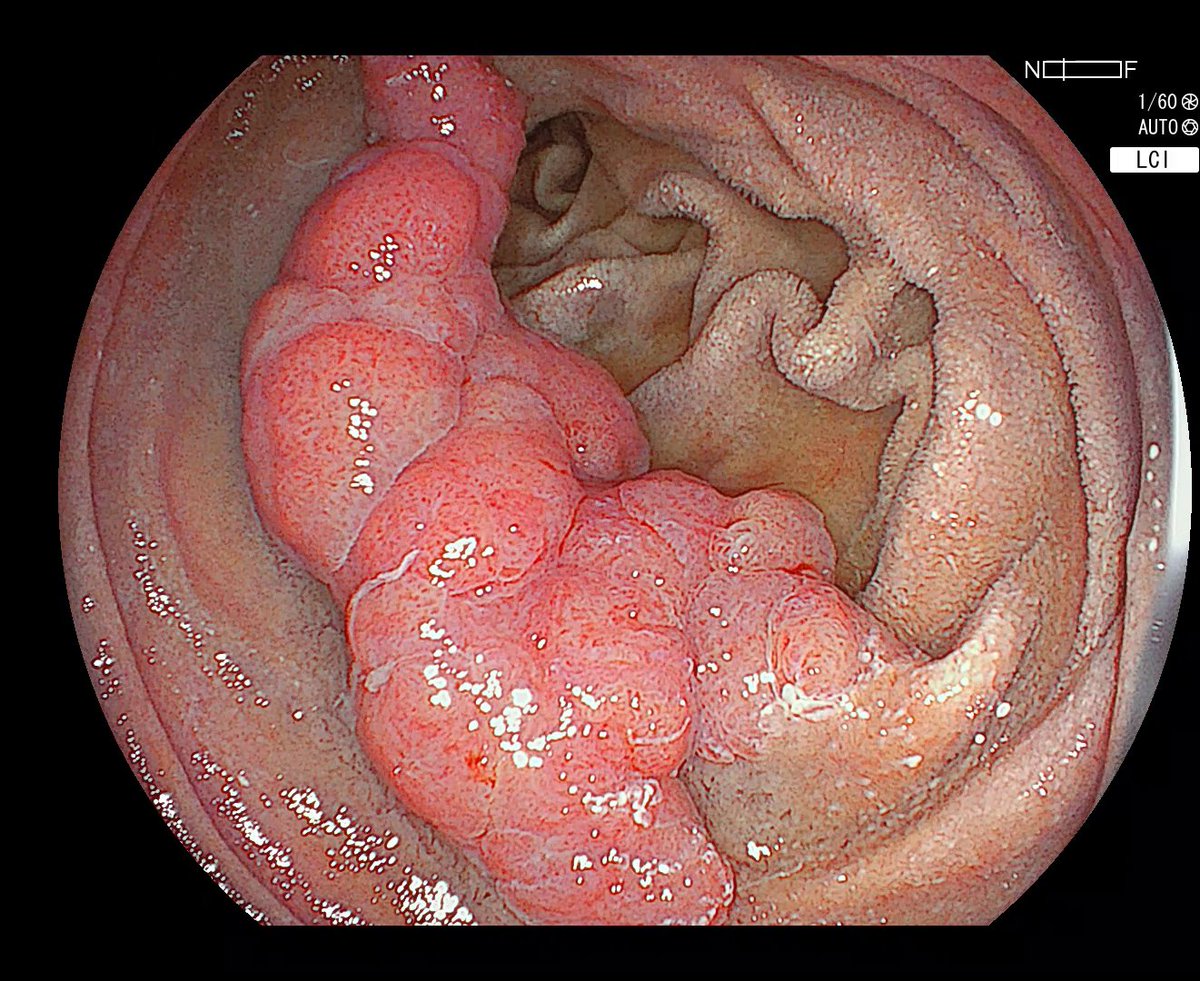

📸interesting case at Geisinger GI by 🌟faculty Dr. Dema Shamoon (Dema Shamoon ): Pt with obstructive jaundice 🌝 → ampullary mass. EUS → FNB 💉: black fluid from specimen. ERCP → Sphincterotomy ✂️exposed a jet-black tumor. Also seen 👀 a Gastric lesion expressing black